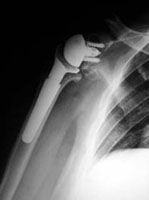

Próetesis de hombroEl Dr. Ángel Villamor, traumatólogo del USP Hospital San José, ha implantado con éxito por primera vez en España la primera prótesis de hombro que respeta la anatomía del paciente, informa el centro hospitalario en un comunicado.

Esta cirugía de hemiartrosplastia mínimamente invasiva ofrece nuevos avances sobre las prótesis utilizadas actualmente en la patología del hombro. Se trata de una técnica de recubrimiento que ha sido desarrollada en Estados Unidos, y de la que en España se habían implantado ocho modelos similares en rodilla y cadera.

En la intervención, que tuvo una duración de dos horas, el equipo quirúrgico retiró de la cabeza humeral del paciente únicamente la porción de cartílago y hueso dañado, preservando la máxima porción ósea y condral posible. El implante y la técnica quirúrgica ha restaurado el cartílago dañado, convirtiéndolo en una superficie lisa, continua y suave, similar a la original.